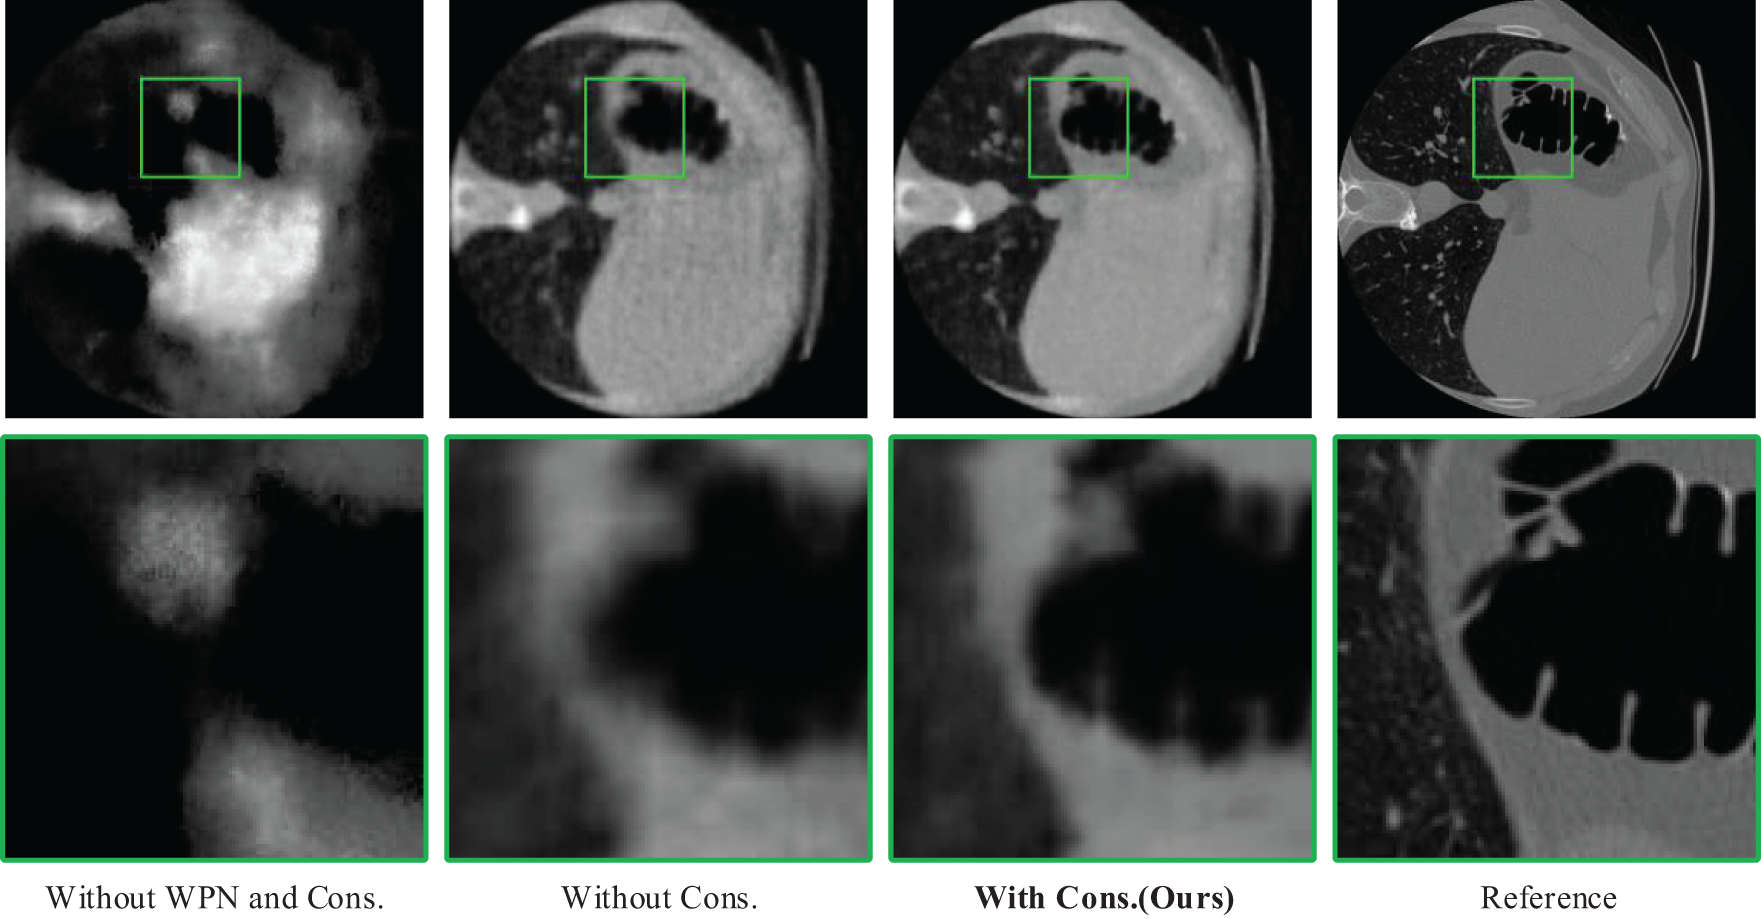

Fig. 8 shows the reconstruction results without both WPN and constraint loss, with WPN and without constraint loss, and with both WPN and constraint loss. As seen from the left two columns of subfigures in Fig. 9, when the constraint loss on the correction rays is absent, WPN combined with spatial geometric information can prevent the corrected rays from diverting to a certain extent and reduce the reconstruction error. Therefore, WPN fusion spatial information is essential to improve the reconstruction quality.

Figure 8: Reconstruction results on Abodomen dataset without using both WPN and Constraint loss, with WPN and without Constraint loss, and with both WPN and Constraint loss

Constraint Loss

As mentioned in Section 3.5, the constraint loss can prevent the predicted corrected ray and CT scene from being distorted simultaneously. As can be seen from Fig. 8, not adding constraint loss can easily cause the reconstructed image to be blurred in detail, although the blur is improved after adding WPN. In general, using Constraint loss can effectively improve the reconstruction quality.